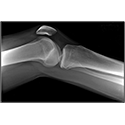

Interactive Radiology